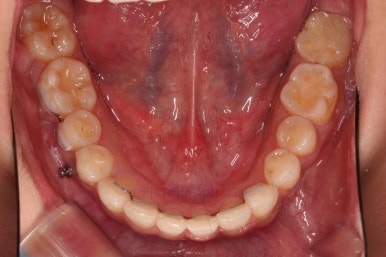

4. 마무리

가지런한 느낌 좋고요.

교합도 잘 맞고 이 뽑은 자리도 틈이 없으며 사랑니 당겨온 자리도 틈새 없이 잘 마무리가 되었네요.

다만 앞니가 예전에 부러져 있어서 형태저긍로 조금 부족하긴 했지만 나쁘지 않았습니다.

연산동교정치과 전후 비교해 보겠습니다.

전반적으로 깔끔하게 임플란트 없이 결손치아 부분을 잘 마무리 했습니다.